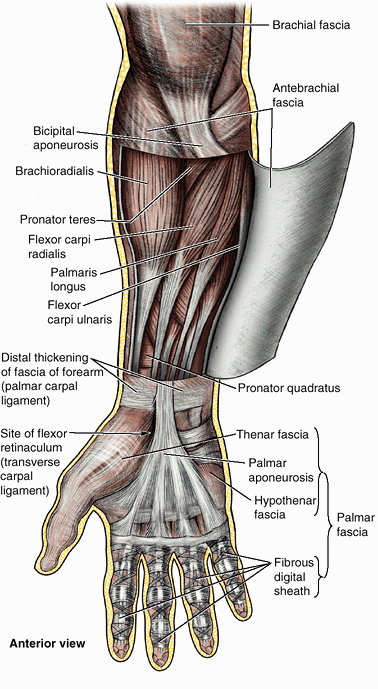

it is continuous superiorly with the deltoid, pectoral, axillary, and

infraspinous fasciae. The brachial fascia is attached inferiorly to the

epicondyles of the humerus and the olecranon of the ulna and is

continuous with the antebrachial fascia, the deep fascia of the

forearm. Two intermuscular septa, the medial and lateral intermuscular septa, extend from the deep surface of the brachial fascia to the central shaft and medial and lateral supraepicondylar ridges of

the humerus (Fig. 6.10B). These septa divide the arm into anterior (flexor) and posterior (extensor) fascial compartments,

each of which contains muscles serving similar functions and sharing

common innervation. As discussed in relation to the fascial

compartments of the lower limb (see Chapter 5),

the fascial compartments of the upper limb are important clinically

because they also contain and direct the spread of infection or

hemorrhage in the limb.

distal ends of the radius and ulna to form a transverse band, the extensor retinaculum,

which retains the extensor tendons in position. The antebrachial fascia

also forms an anterior thickening, which is continuous with the

extensor retinaculum but is officially unnamed; some authors identify

it as the palmar carpal ligament (Fig. 6.10D). Immediately distal and at a deeper level to the latter, the antebrachial fascia is also continued as the flexor retinaculum (transverse carpal ligament).2

This fibrous band extends between the anterior prominences of the outer

carpal bones and converts the anterior concavity of the carpus into a carpal tunnel, through which the flexor tendons and median nerve pass.

is thick, tendinous, and triangular and it overlies the central

compartment of the palm. Its apex, located proximally, is continuous

with the tendon of the palmaris longus (when it is present) (Fig. 6.10A).

The aponeurosis forms four distinct thickenings that radiate to the

bases of the fingers and become continuous with the fibrous tendon

sheaths of the digits. The bands are traversed distally by the superficial transverse metacarpal ligament, which forms the base of the palmar aponeurosis. Innumerable minute, strong skin ligaments (L. retinacula cutis) extend from the palmar aponeurosis to the skin (see the Introduction). These ligaments hold the palmar skin close to the aponeurosis, allowing little sliding movement of the skin.